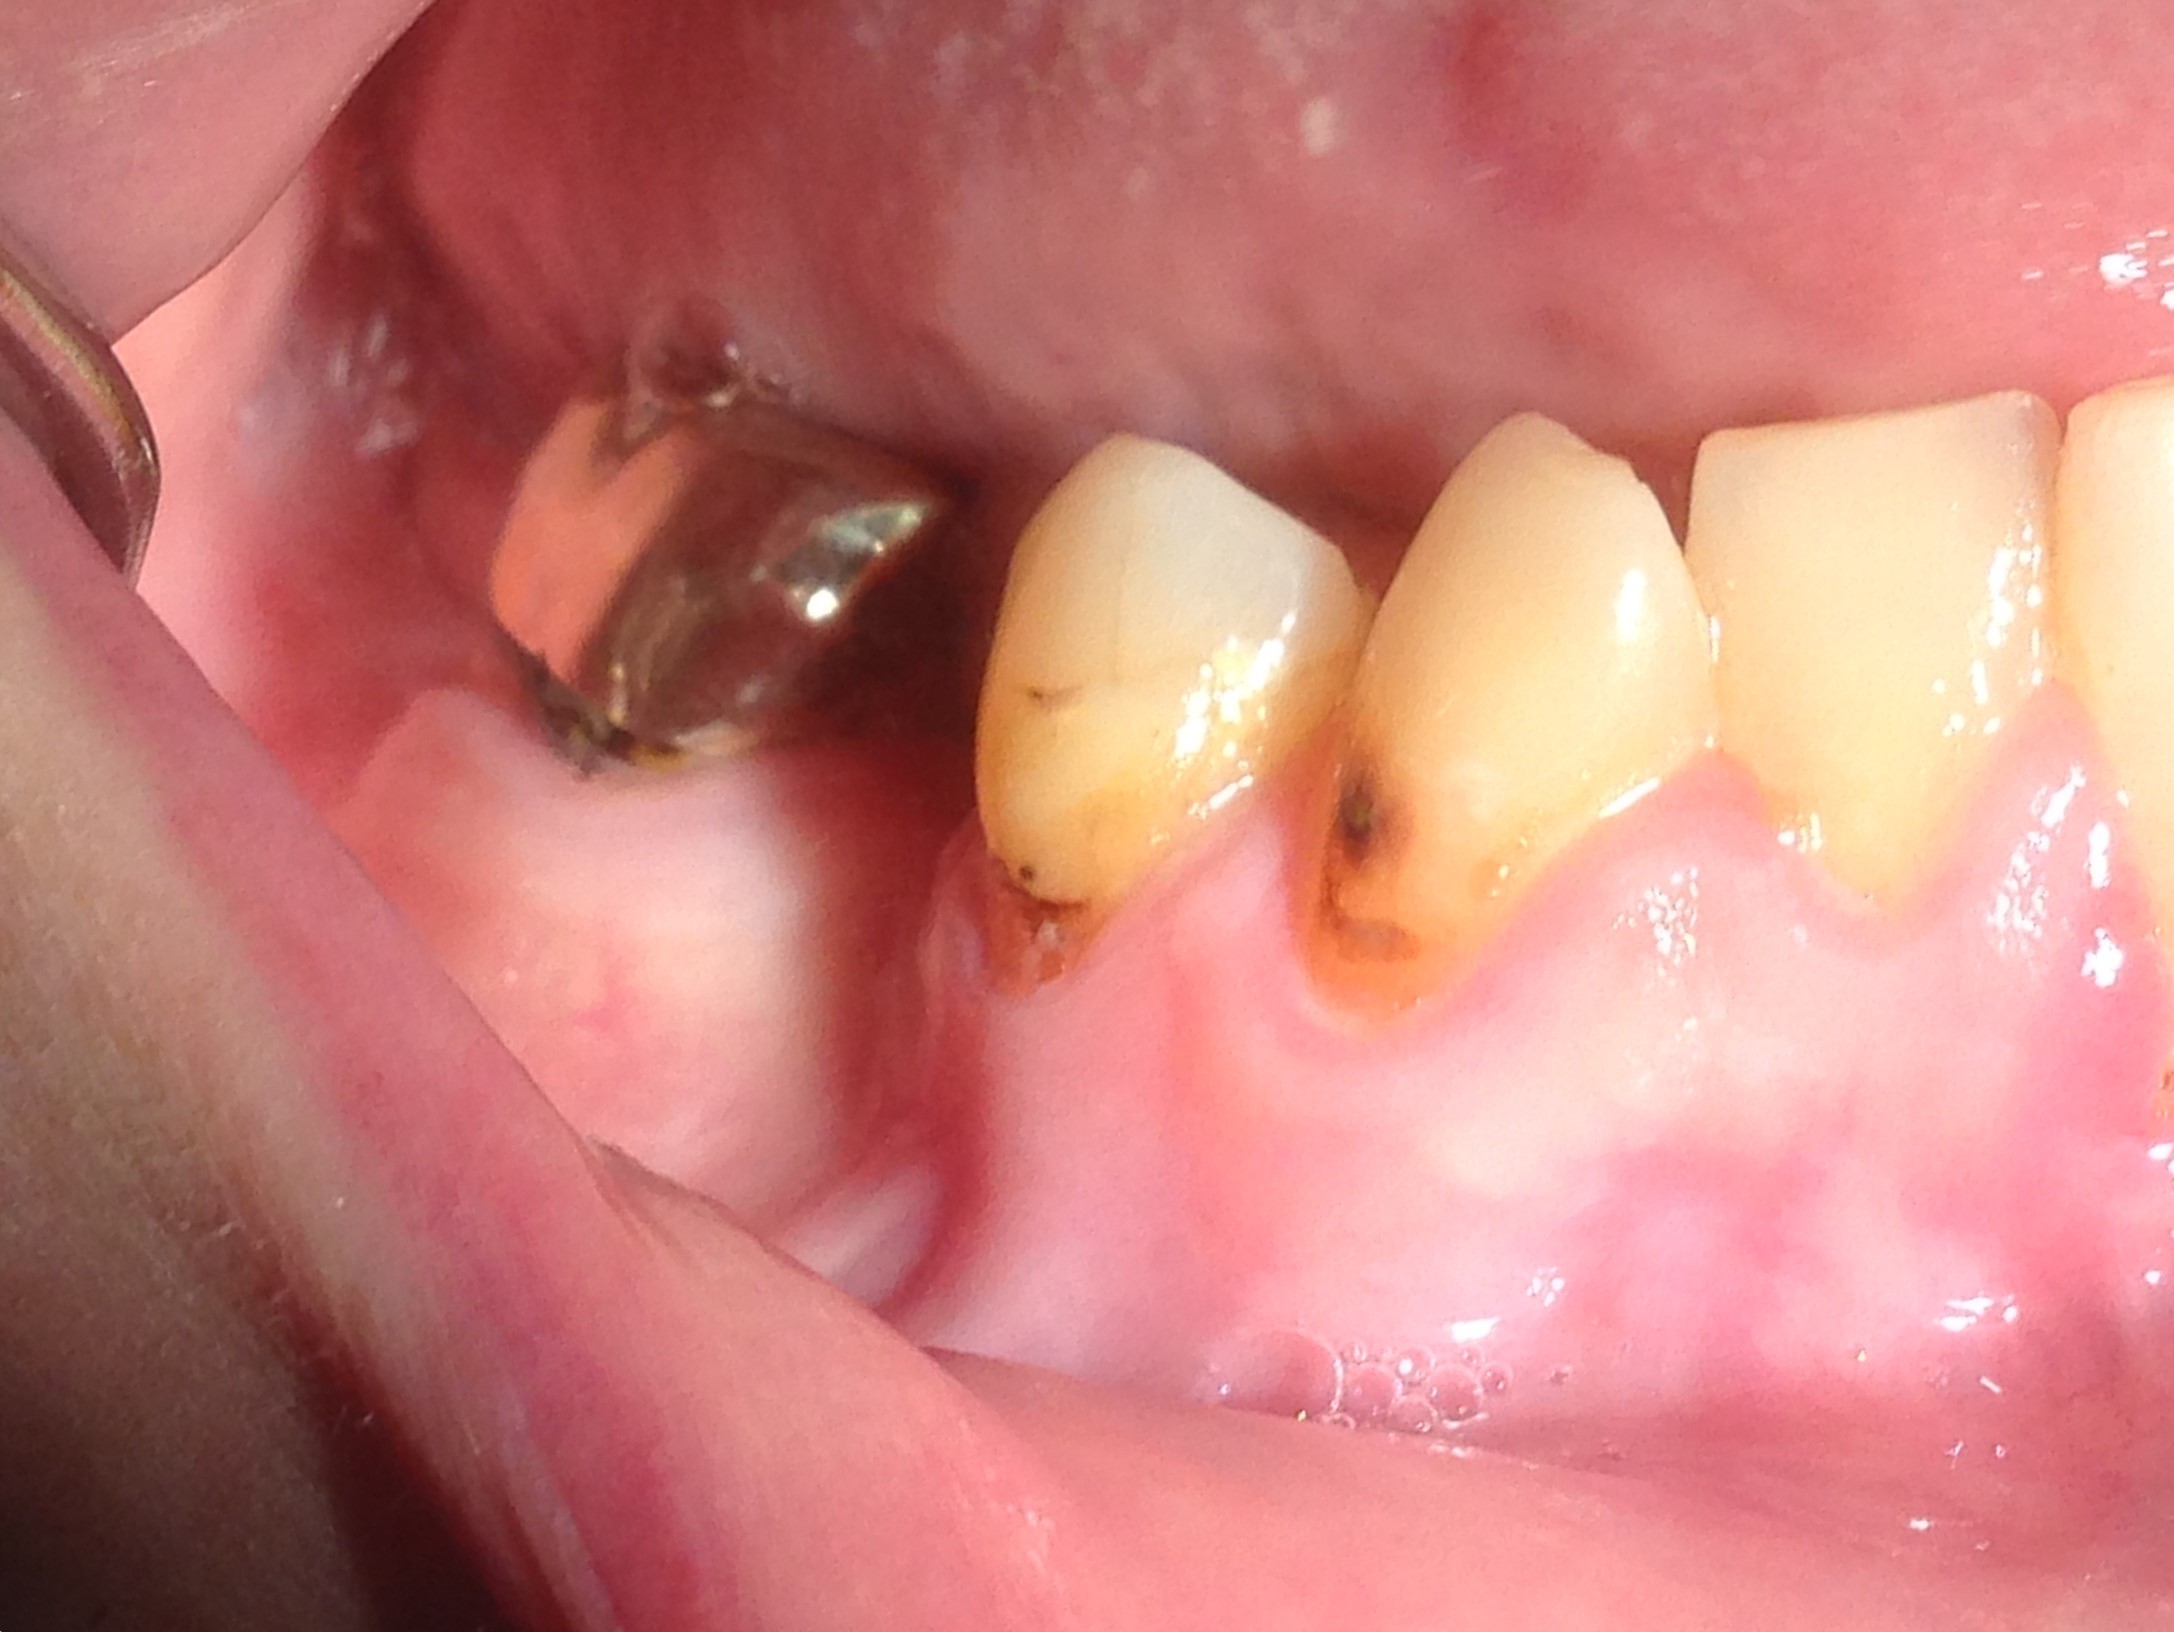

The patient in Figure 10 through Figure 12 was pregnant when she presented for dental treatment. The pregnancy was unplanned and she had had a lack of prenatal care. Continuing meth use during the pregnancy resulted in a positive toxic baby. She stated that she had just stopped using meth and had entered a rehabilitation facility a few days before. She was brought to the author’s clinic with a toothache. Note that as seen in these images, extreme accumulation of plaque, lack of oral hygiene, and severely decayed and missing teeth are classic manifestations in meth users.

Fig 10. Accumulation of soft plaque is typical of oral hygiene neglect associated with the use of methamphetamine.

Figure 10

Fig 11. Note demineralization of smooth surfaces, carious lesions at the gingival margins, and associated inflammation of the periodontium.

Figure 11